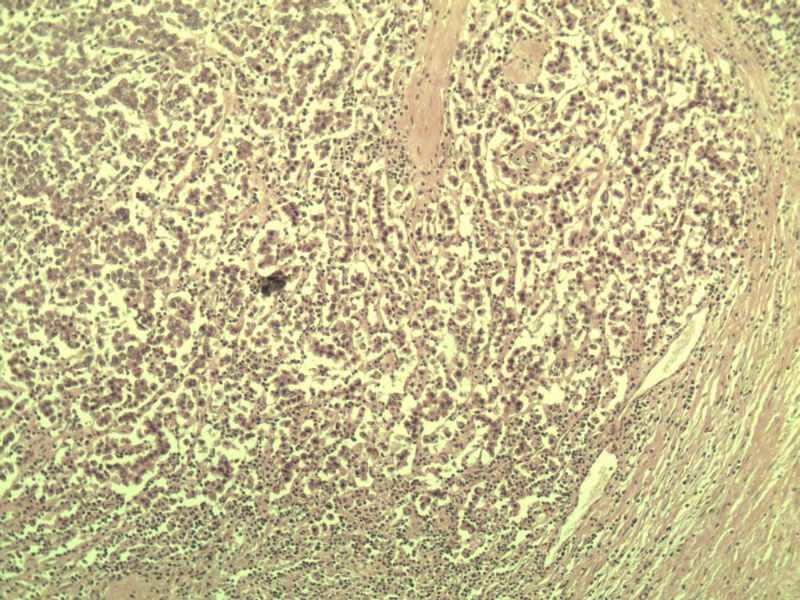

男 27岁 腹腔隐睾 5*3*2 cm, 切面灰红灰黄、实性、质中,请各位老师看看,是精原细胞瘤吗?感觉不像.